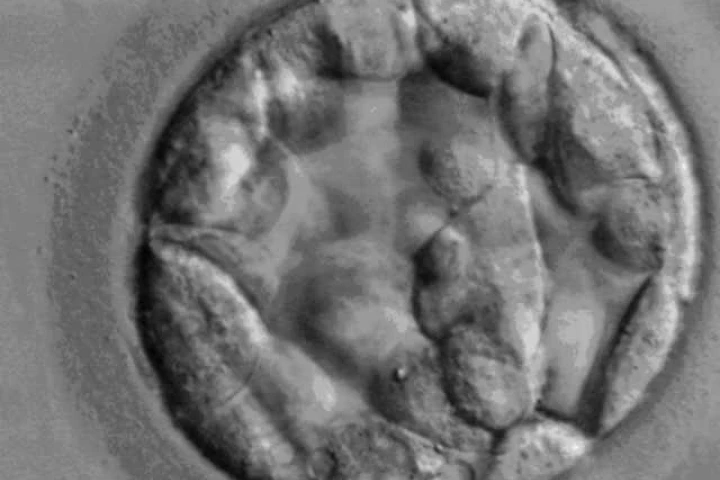

Ein fünf Tage alter menschlicher Embryo

Die von der zuständigen britischen "HFEA"-Behörde (Human Fertilisation and Embryology Authority) genehmigten Experimente werden innerhalb der ersten sieben Tage an einer befruchteten menschlichen Eizelle vorgenommen, berichten Medien. Forscher am Francis Crick Institut in London rechtfertigen ihre umstrittene Arbeit damit, dadurch Erkenntnisse über die Zell-Entwicklung der Embryonen zu gewinnen, die medizinisch von Bedeutung sein würden. Die menschlichen Embryonen werden nach Ablauf der Experimente innerhalb einer Woche getötet, oder, wie die Forscher sagen, "zerstört". Ähnliche Genmanipulationen am menschlichen Leben sind weltweit sonst nur in China zugelassen.